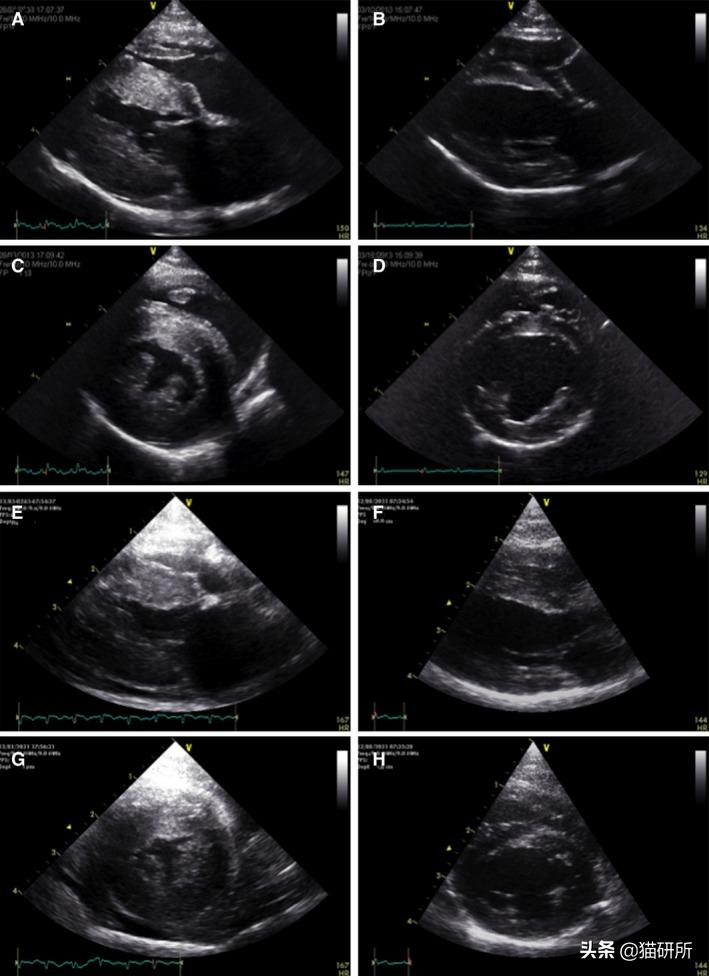

2018年,J.Novo Matos等人在对TMT和HCM患猫的研究中发现:

● 患猫们的临床症状和超声心动图没有特异性差异;

2例TMT患猫 最初左室壁厚度+心包积液(ACEG+EG) 7个月后,心脏形态正常(BDFH)